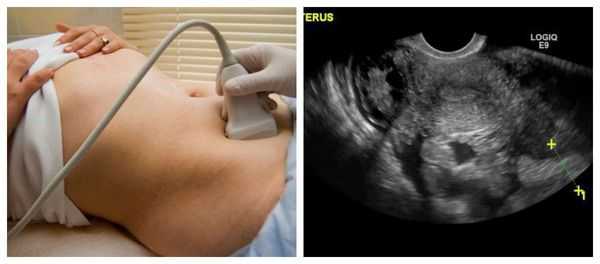

- Ультразвуковое исследование (УЗИ) матки и плода - метод позволяет обнаружить истончение мышечного слоя матки в каком-либо месте, оценить наличие и состояние послеоперационных рубцов.

- Тщательное наблюдение за имеющимся рубцом на матке с помощью ультразвукового исследования (УЗИ) каждые 7-11 дней, начиная с 20-22 недель беременности.

- Контроль за состоянием плода и рубца на матке во время самопроизвольных родов (кардиотокография, УЗИ матки в области послеоперационного рубца).